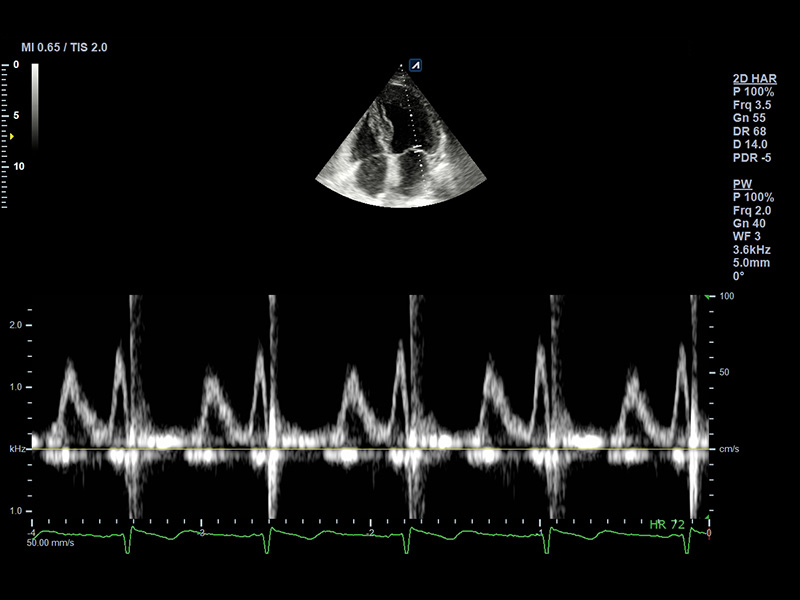

CW5.0

Pencil type transducer (5.0MHz)

Application:

Cardiac

CW2.0

Pencil type transducer (2.0MHz)

Application:

Cardiac